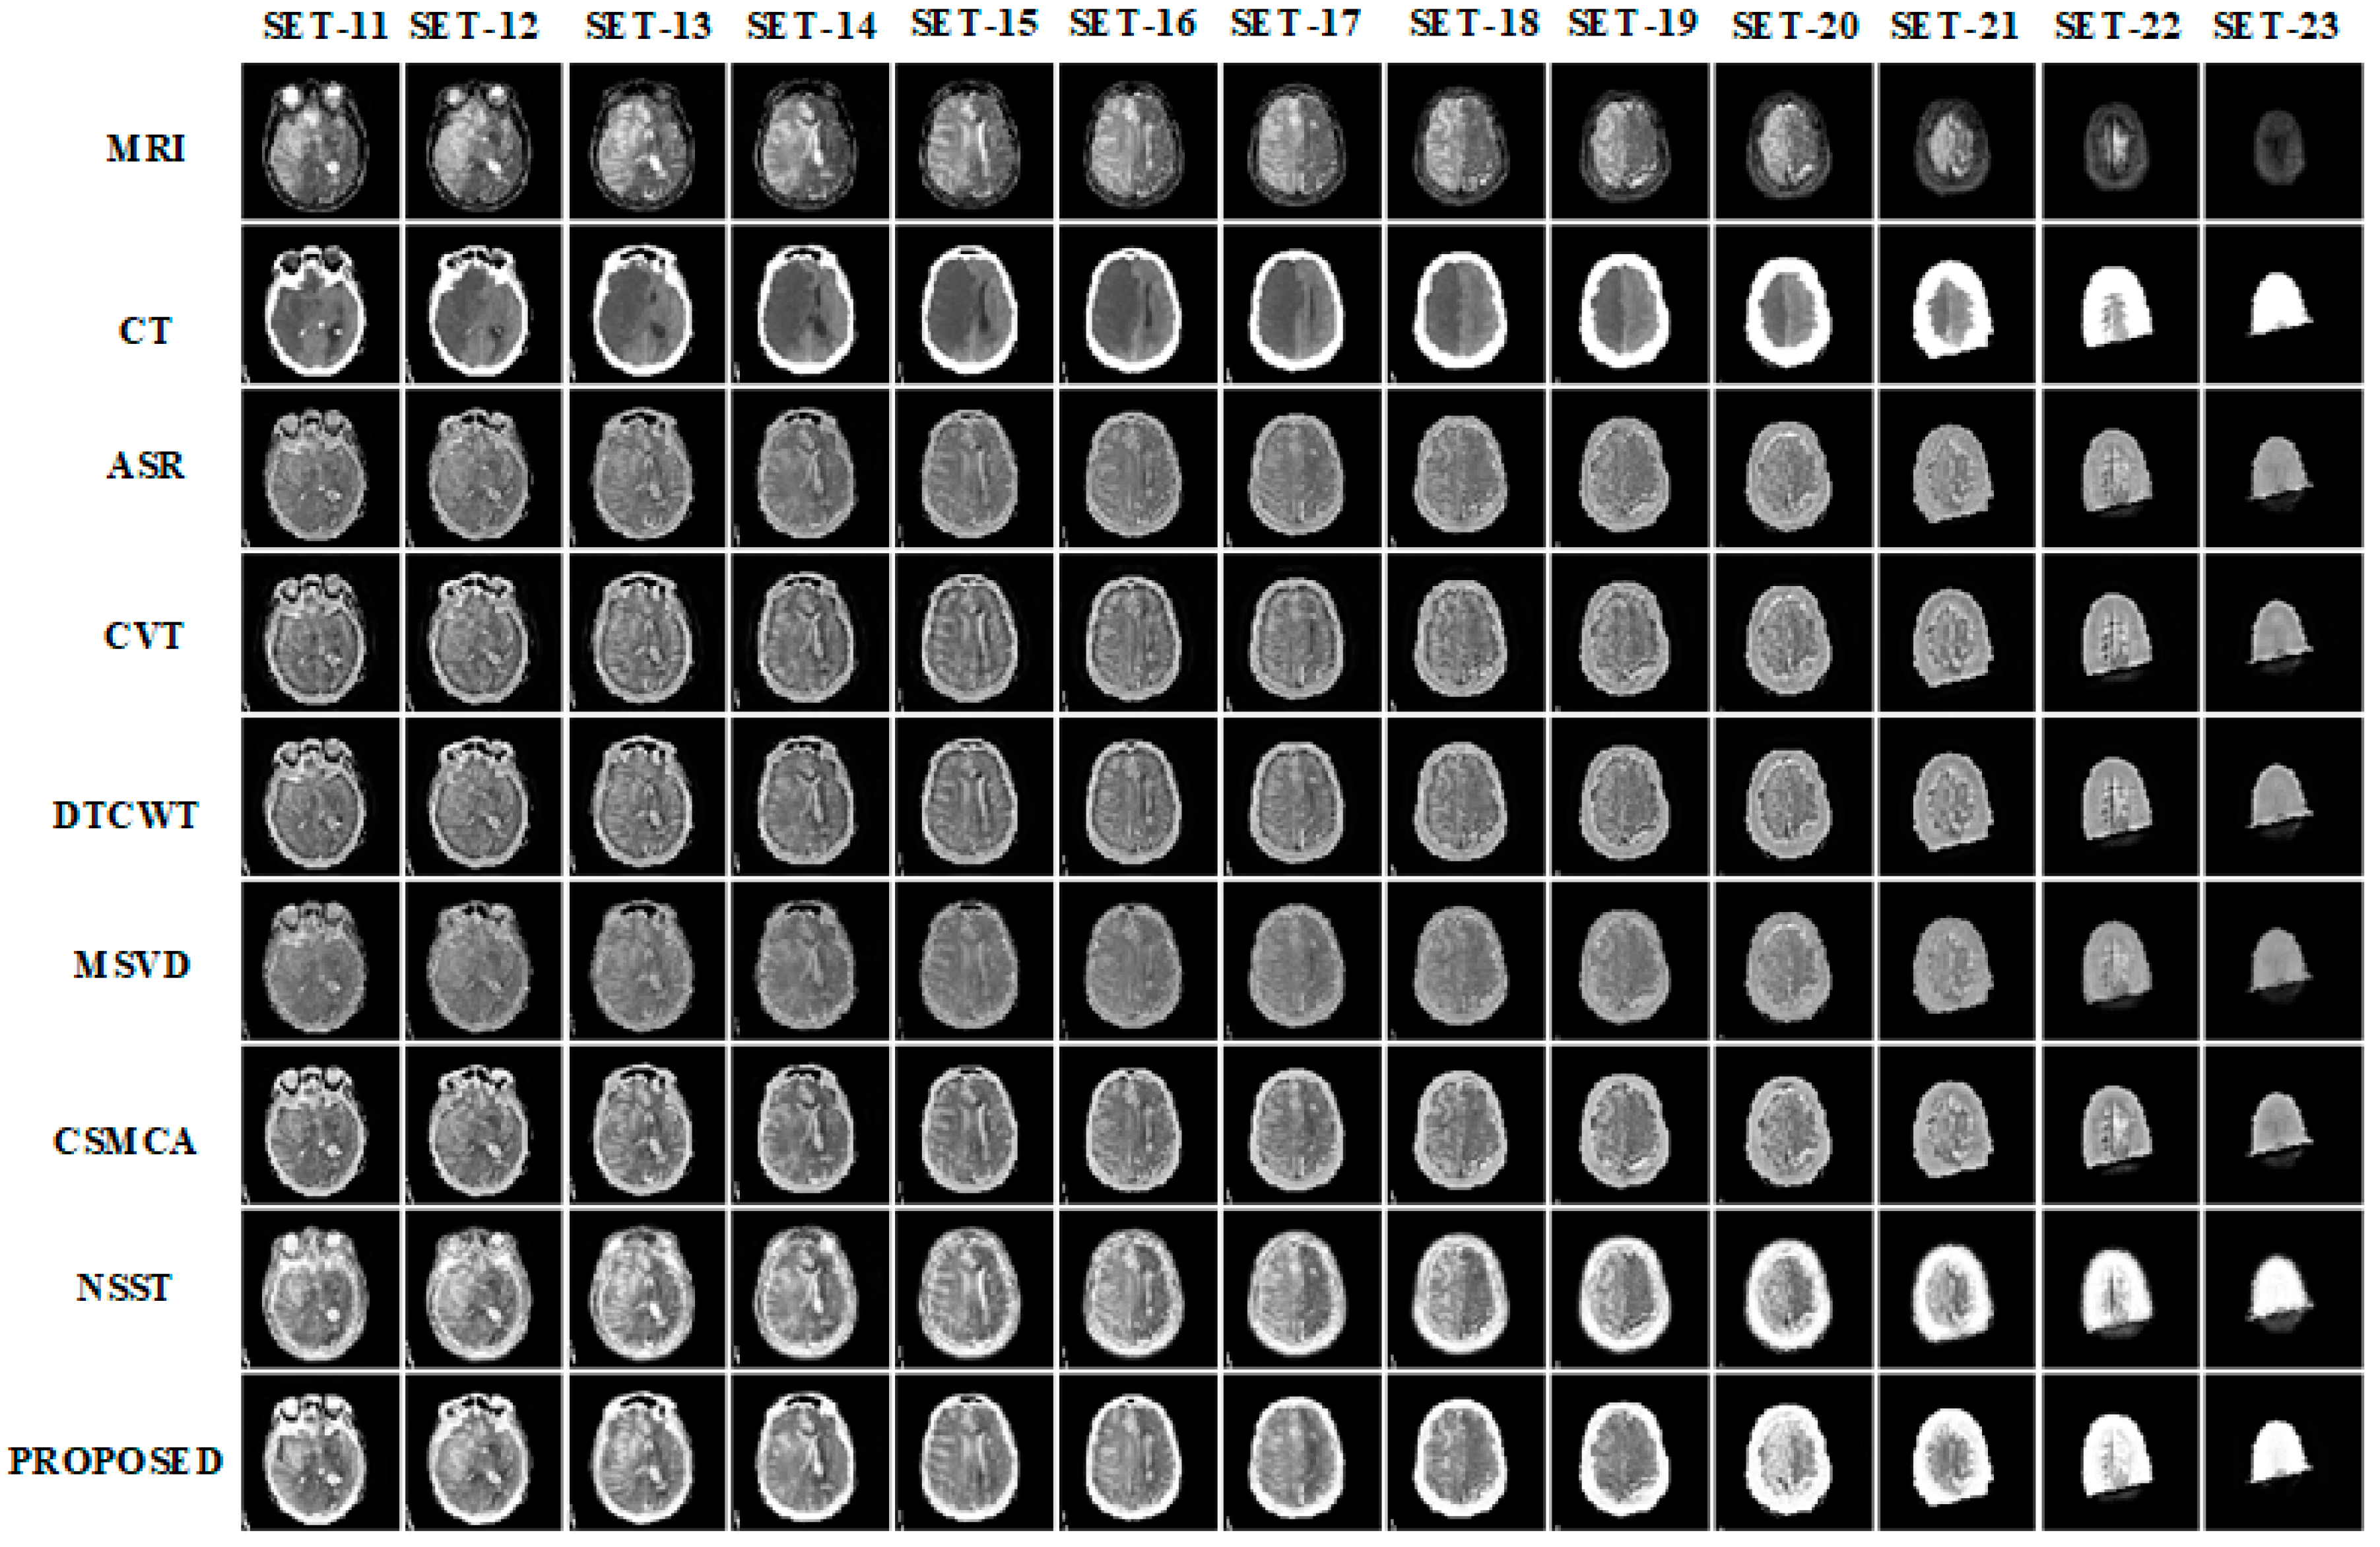

3.1. Subjective Assessment

3.2. Objective Assessment